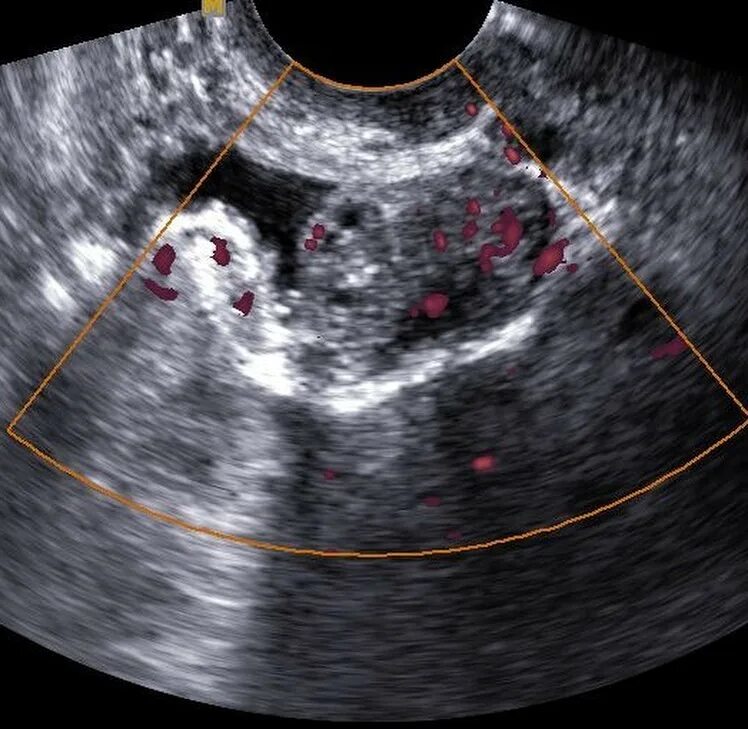

Что такое признаки внутреннего эндометриоза матки